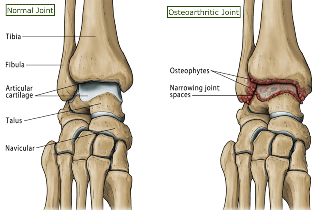

Arthritis